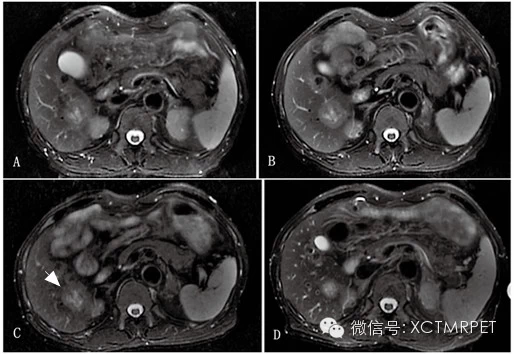

图 2 结肠癌肝转移患者,男性,64 岁(与图1 为同一患者)。A-D:分别为化疗前、化疗开始3、7 及42 天连续b=800s/mm2 ADC 图像;显示肝右叶转移灶动态变化。